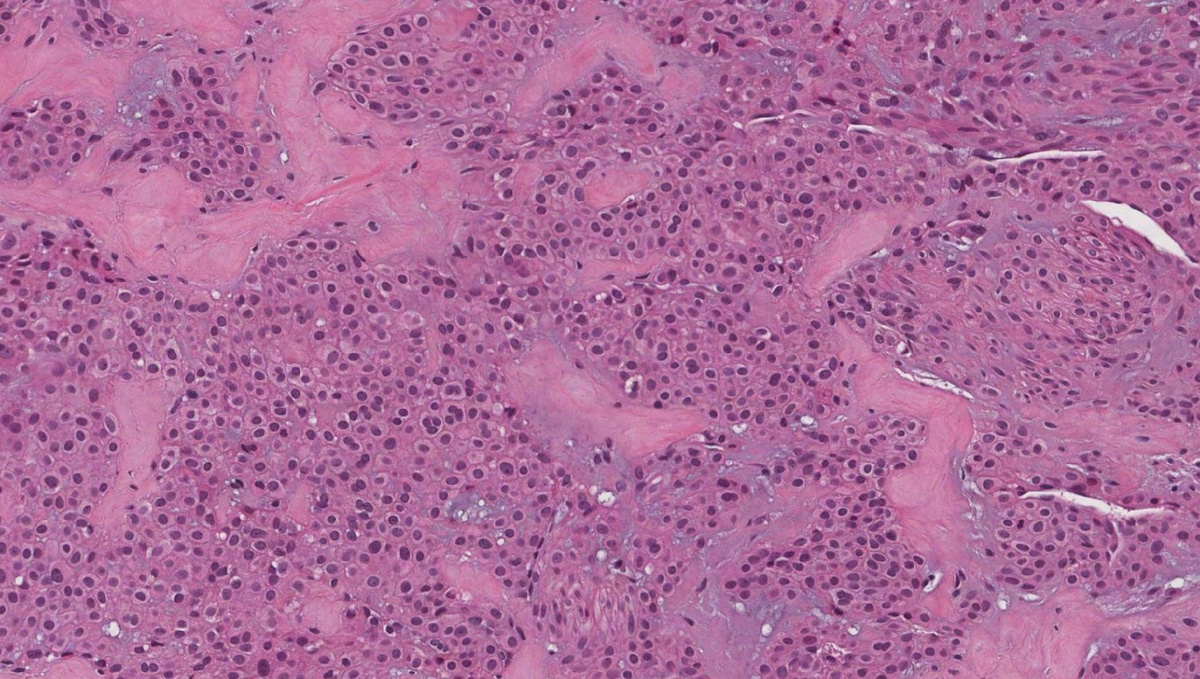

Хорошо отграниченная трехкомпонентная опухоль: гломусные клетки, сосуды и гладкомышечные клетки

Солидные гломусные опухоли (75% случаев): преобладают гломусные клетки, слабо выражена сосудистая сеть и редкие гладкомышечные клетки.

• Ветвящиеся капилляры, выстланные эндотелиальными клетками, муфтообразно окруженные монотонными гломусными клетками, формирующими гнезда, пласты или трабекулы в гиалинизированной или миксоидной строме Гломусные клетки округлой формы с четкими границами, амфофильной/эозинофильной цитоплазмой и округлыми, центрально расположенными, круглыми ядрами. Гомогенный хроматин, ядрышки незаметны

• Очень редкие митозы

Обязательные: мономорфные округлые или эпителиоидные клетки с центрально расположенным круглым ядром с четкими клеточными границами, образуют периваскулярные гнезда (муфты); злокачественные гломусные опухоли можно узнать по прилежащему на периферии доброкачественному компоненту, а также по характерным веретеноклеточным или круглоклеточному саркоматозному фенотипу; в злокачественных вариантах без доброкачественного компонента требуется ИГХ или молекулярная диагностика.